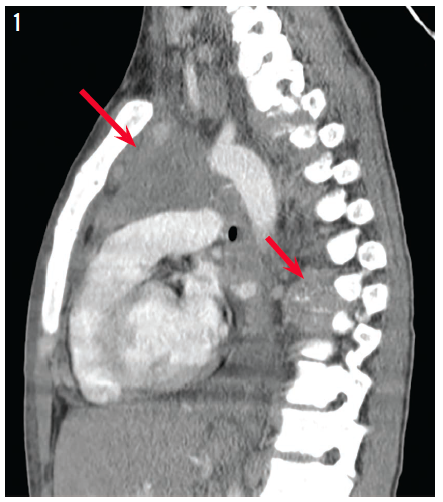

Achalasia

Sumreen Hussain, MD; Jason Dranove, MD

A 6-year-old boy with poorly controlled asthma presented with difficulty breathing, persistent vomiting, and a 7-pound weight loss.